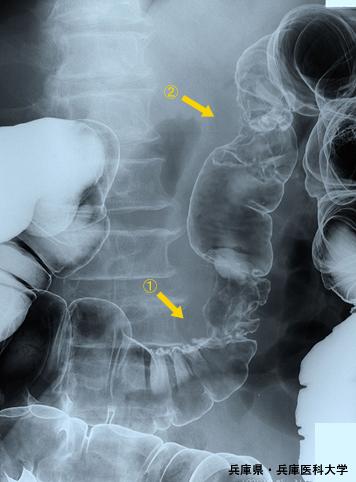

疾病(病理主体)的分类恶性上皮性肿瘤/腺癌

部位(按器官分)大肠/横结肠

检查方法X线

肿瘤的肉眼分类2型(溃疡局限型)/

肿瘤最大直径40以上

肿瘤的深度ss(a1)

多发性肿瘤(同一器官)有(同时性)